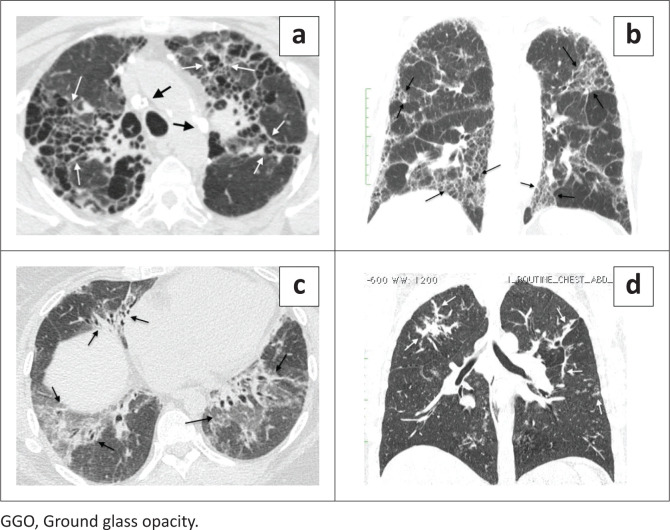

Results: Peripheral fibrosis was most common (291/396, 73.5%), usually caused by idiopathic pulmonary fibrosis (IPF) and connective tissue diseases-related interstitial lung disease (CTD-ILD) but occasionally by hypersensitivity pneumonitis (HP), idiopathic nonspecific interstitial pneumonia (iNSIP) and asbestosis. Peripheral fibrosis with honeycombing was usually IPF and without honeycombing, was usually CTD-ILD. Peripheral fibrosis with pleural plaques was always asbestosis. Peripheral fibrosis with oesophageal dilatation was usually connective tissue diseases. Consolidative-like peripheral fibrosis was CTD-ILD. Axial fibrosis (61/396, 15.4%) was usually sarcoidosis, HP, CTD-ILD or silicosis. Axial fibrosis with predominantly consolidative-like fibrosis, honeycombing, or reticulation was usually sarcoidosis. Axial fibrosis predominated by ground glass opacity was usually HP or CTD-ILD. Lymph node calcification or short axis > 17 mm increased the probability that axial fibrosis was due to sarcoidosis. The non-specific fibrosis phenotype was uncommon (44/396, 11.1%), usually CTD-ILD (25/44, 57%) but also HP, IPF, iNSIP or asbestosis.

Conclusion: Patterns of lung fibrosis provide guidelines to identify the cause.